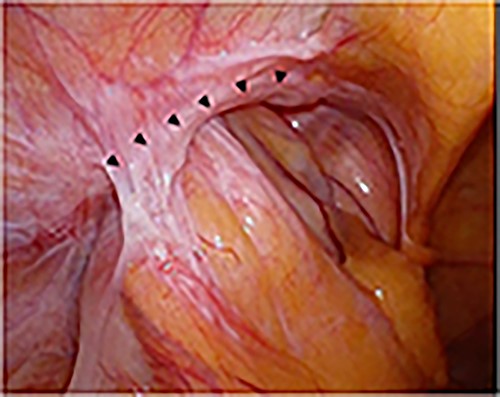

A laparoscope was inserted through a 12-mm umbilical port. In the laparoscopic view, on the left side, the sigmoid colon had retracted into the hernia lateral to the left epigastric artery, suggesting a sliding hernia of the sigmoid colon (Fig. 6). The size of the hernial orifice was ~30 mm. On the right side, the direct inguinal hernia was 20 mm in size. Accordingly, 12-mm ports were created at the level of the umbilicus aligning with the left and right mid-clavicle. The left side had been repaired first. After peritoneal incision and preperitoneal space dissection, the inner inguinal ring was found to be too small relative to the physical findings. Instead, the hernial orifice was observed under the conjoint tendon toward the ventral dorsal direction (Fig. 7). Based on the aforementioned findings, the left interparietal inguinal hernia was reconfirmed. Subsequently, preperitoneal repair of the hernia was performed with a mesh using the same surgical procedure as that for a standard TAPP repair. The hernia was repaired in the same way on the right and left sides. On postoperative Day 1, the patient resumed oral intake. Further, on postoperative Day 2, he was discharged uneventfully.

Intraoperative findings of the left inguinal region after peritoneal incision; the black triangles indicate the hernial orifice; the dotted circle indicates the assumed hernia sac; the black cross indicates the internal inguinal ring.